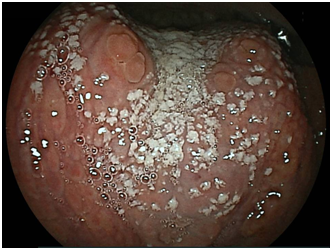

We detected 11 cases of superficial squamous cell carcinoma of the base of the tongue between April 2012 and March 2016. All the patients were complicated with current (n=3) or previous (n=8) esophageal squamous cell carcinoma. The patient characteristics are shown in Table 1. The mean age of the patients was 63.7years (range, 49-73years), and all patients were male. Four cases were diagnosed using trans-nasal endoscopy with the FICE system, seven cases were diagnosed using trans-nasal endoscopy with the LASERIO system. The average time to complete a thorough examination for one patient was approximately from 1 to 2minutes, regardless of the presence of abnormal findings. Biopsy specimen were obtained in all patients, and diagnosed as squamous cell carcinoma pathologically. Table 2 shows the treatment results. Five lesions were flat type (Figure 4A), four were elevated (Figure 4B), and two were depressed (Figure 4C). Regarding the tumor size, eight were T1, three were T2. No lymph node metastasis was detected in any case. Six cases were treated by endoscopic laryngo-pharygeal surgery,15 and 3 cases were treated by chemo-radiotherapy. One case was followed because of esophageal cancer. One case was treated by trans-oral robotic surgery at another hospital. For the seven resected specimens, the median tumor thickness was 800μm (range, 250-3000μm), and the median tumor diameter was 11mm (range, 10-25mm). Histologically, two of these lesions were squamous cell carcinoma in situ, five showed microinvasion of the subepithelial tissue. During a median follow-up period of 26months (range,11-56months), 1 patient, which patient’s tumor thickness was 3000μm, developed lymph node metastasis, which was treated by neck lymphadenectomy and chemo-radiotherapy. Three of the 11 patients cases were died of another disease, and 8 were alive as drafting this manuscript.

Figure 4B Elevated type.